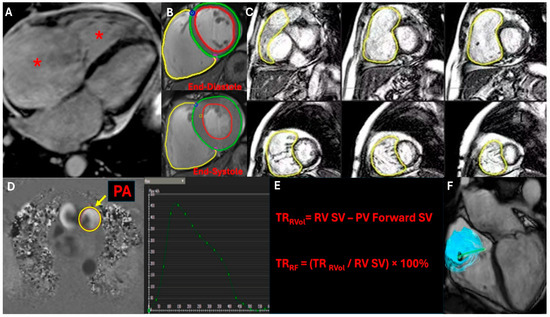

Outcomes of Mechanical Mitral Valve Replacement with Preservation of Posterior Leaflet in Patients with Reduced Left Ventricular Function

Surgeries 2026, 7(1), 24; https://doi.org/10.3390/surgeries7010024 - 14 Feb 2026

Background: Compromised left ventricular function presents unique challenges during mitral valve surgery. Recent evidence suggests that subvalvular apparatus preservation might enhance postoperative recovery in high-risk populations. Methods: This prospective observational investigation (Hue Central Hospital, March 2015–September 2016) evaluated 87 patients undergoing mechanical mitral

Background: Compromised left ventricular function presents unique challenges during mitral valve surgery. Recent evidence suggests that subvalvular apparatus preservation might enhance postoperative recovery in high-risk populations. Methods: This prospective observational investigation (Hue Central Hospital, March 2015–September 2016) evaluated 87 patients undergoing mechanical mitral valve replacement with posterior leaflet preservation. Participants were stratified into two groups: reduced ejection fraction (EF ≤ 50%, n = 38) and preserved EF (>50%, n = 49). Comprehensive clinical and echocardiographic assessments were conducted at 1, 3, 6, and 12 months postoperatively. Statistical analysis employed parametric and non-parametric methodologies, with survival analyzed via Kaplan–Meier techniques. Results: The reduced EF cohort demonstrated significant improvement in contractile performance from 48.8 ± 5.2% preoperatively to 61.6 ± 7.2% at 12 months (p < 0.05). Ventricular dimensions decreased notably from 59.2 ± 6.6 mm to 47.6 ± 4.0 mm (p < 0.05). Hospital mortality was 2.3% (2 patients). Twelve-month survival rates reached 94.66% and 97.96% for reduced and preserved EF groups, respectively, without significant inter-group differences (p = 0.42). All surviving participants achieved functional status in NYHA class I or II. Conclusions: Mechanical mitral valve replacement with posterior leaflet preservation represents an effective approach for patients with reduced ventricular performance, promoting substantial improvement in cardiac function and excellent clinical outcomes.